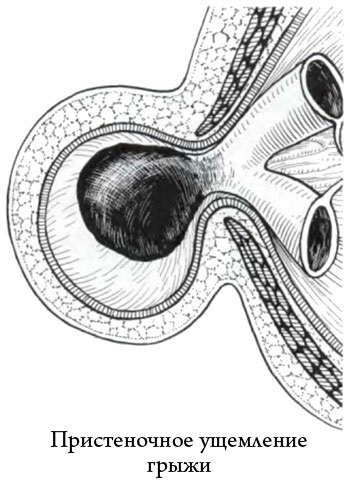

4. Lângă perete sau hernie ciupit Richter

Cu acest tip de patologie este supusă încălcare nu este întregul intestin, doar marginea ei.

Când hernii inghinale sunt rare.